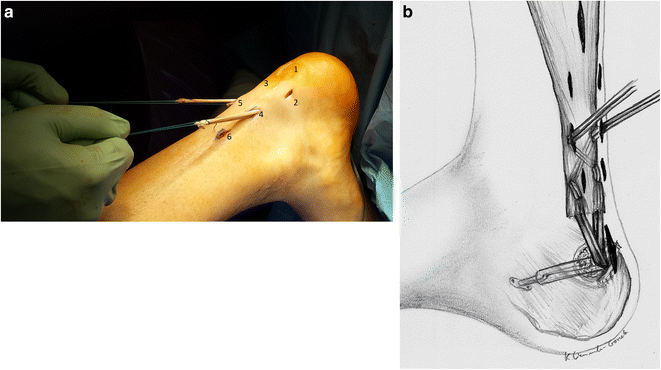

الجراحة محدودة التدخل (Minimally Invasive / Percutaneous Repair)

تعتمد الجراحة طفيفة التدخل على عدة فتحات صغيرة بدلًا من شق كبير، ثم يتم تمرير الخيوط الخاصة عبر الجلد لإعادة تقريب طرفي الوتر.

هذه التقنية تقلل من إصابة الأنسجة المحيطة. كما تُخفض احتمالية العدوى ومضاعفات الجرح، كما تساعد على تسريع العودة للحركة المبكرة ضمن برنامج تأهيلي منظم.

في عام 2026، تعتمد الأساليب الحديثة على خيوط عالية القوة وتقنيات تثبيت متطورة توزع الشد على الوتر بشكل متوازن. مما يقلل خطر إعادة القطع (Re-rupture) ويُحسن النتائج الوظيفية طويلة المدى.

كما أصبح الاتجاه الحالي يميل إلى بدء التحميل الحركي المبكر تحت إشراف طبي، بدلًا من التثبيت الطويل، وذلك نظرًا لما أثبتته الدراسات من أن الحركة المنظمة تُحفز التئام الأوتار بشكل أفضل.